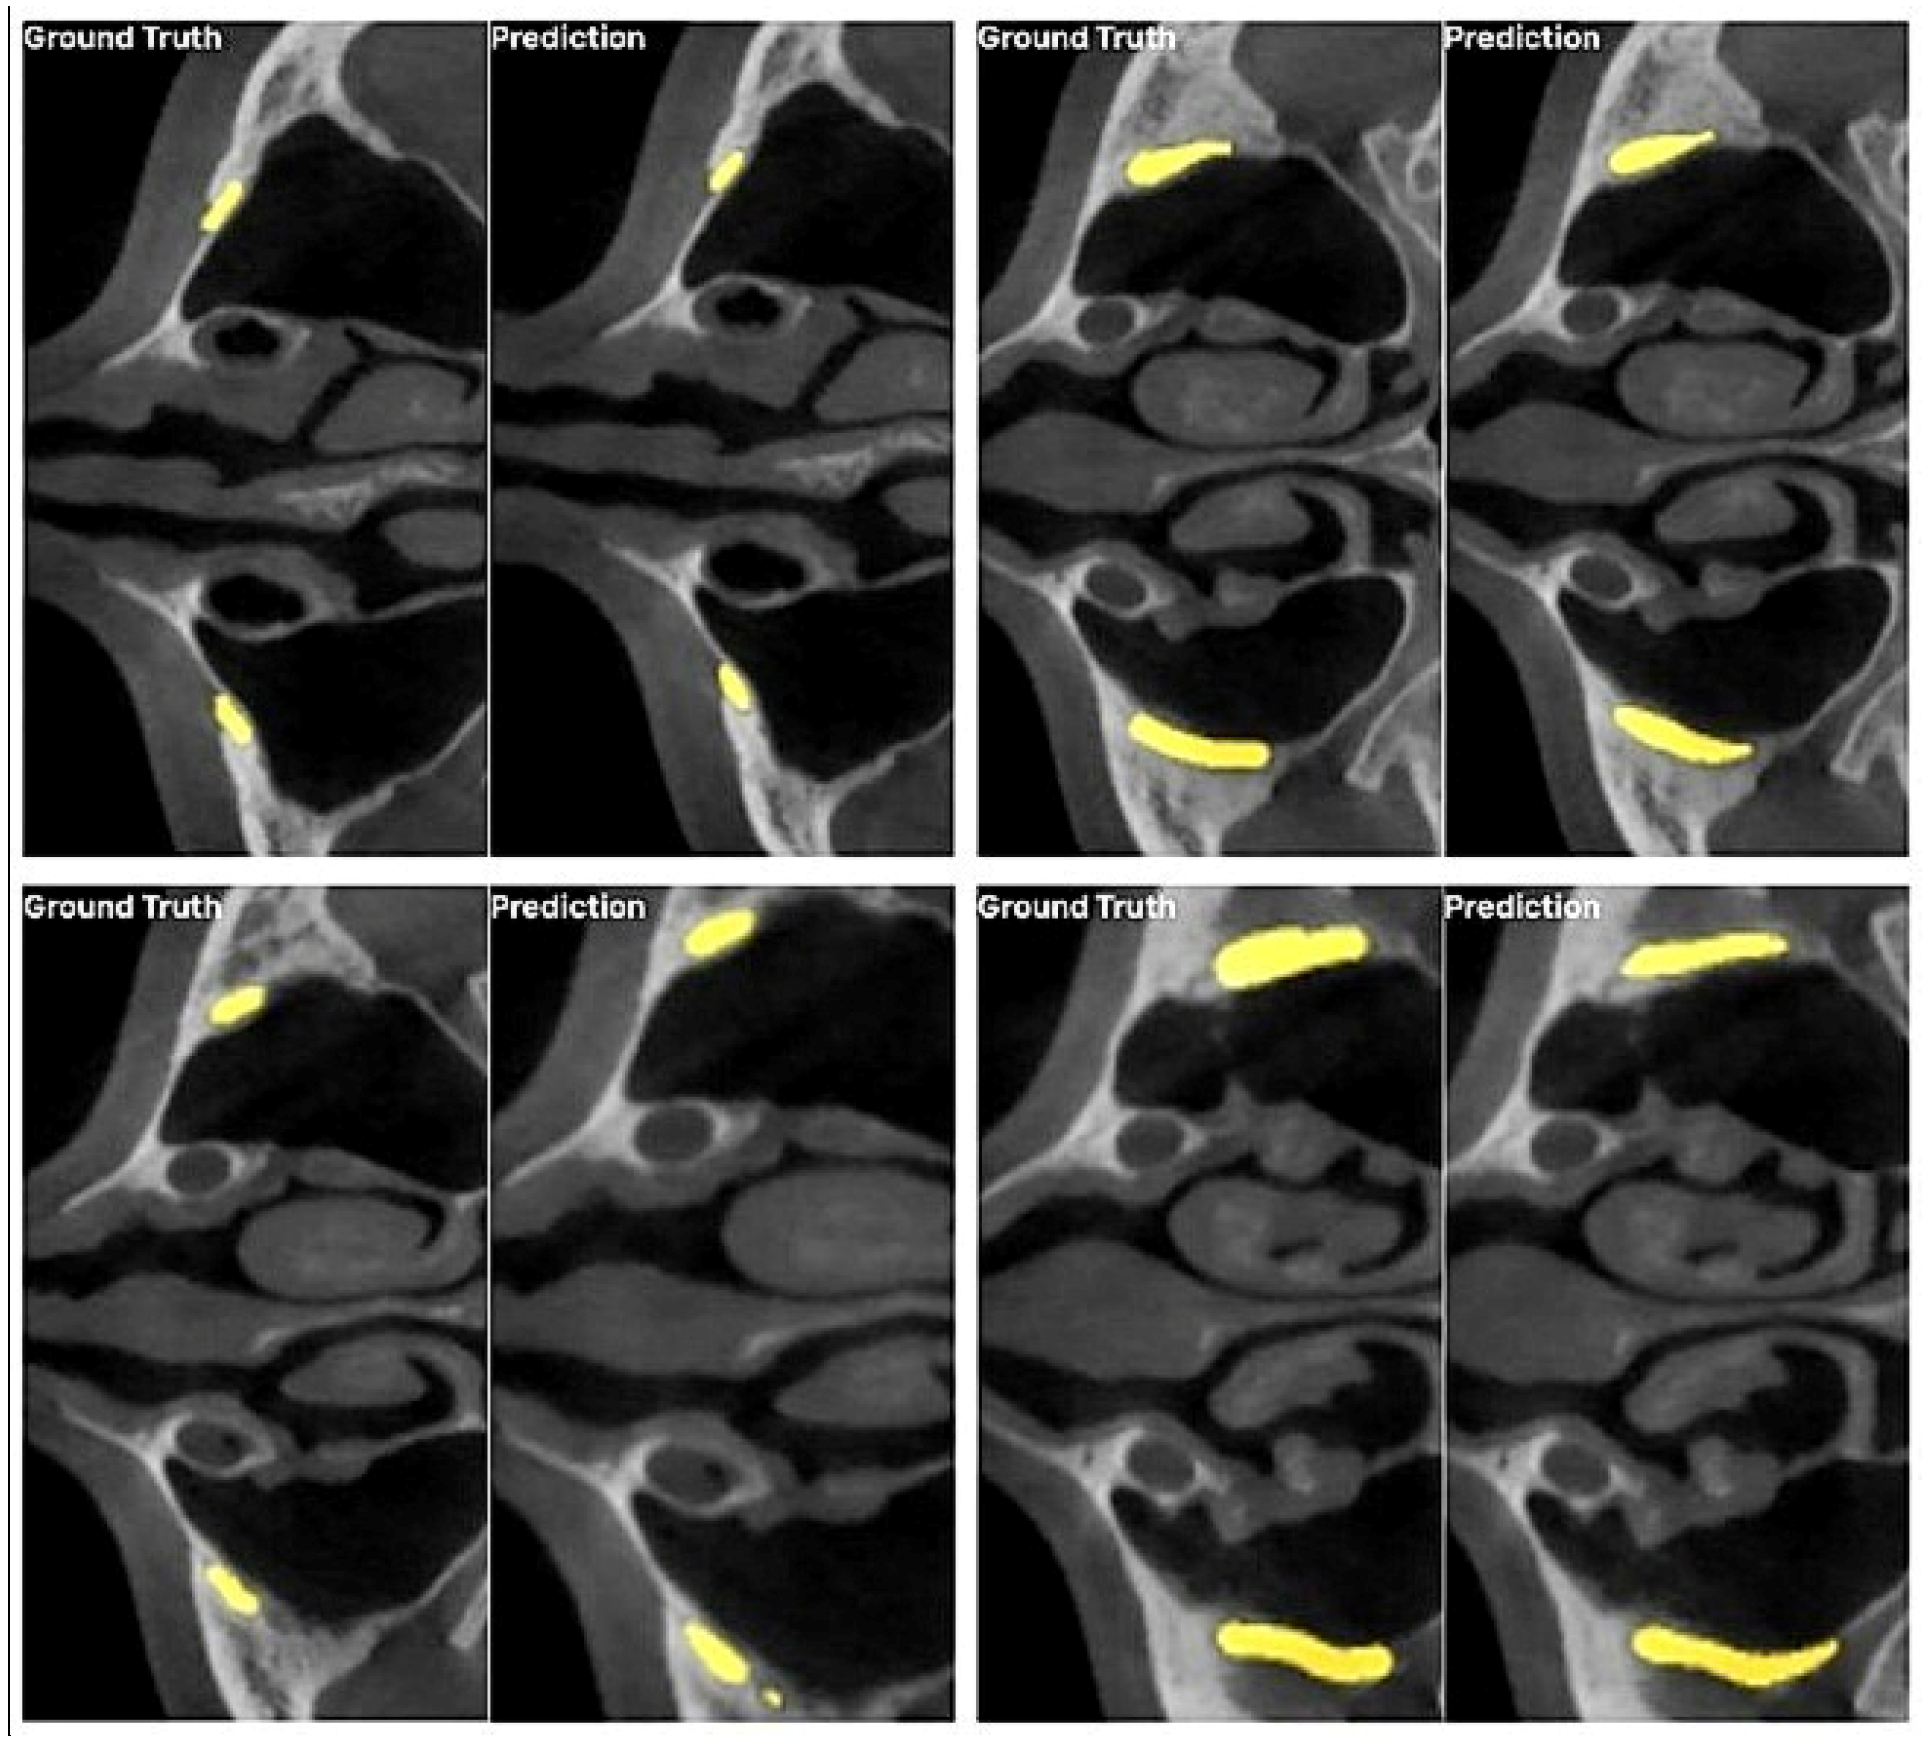

3. Results